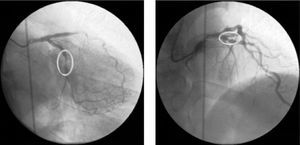

Immediately afterwards there was a drop in arterial blood pressure and the angiogram revealed other new lesions and reduced flow throughout the coronary tree. The patient went into cardiogenic shock and the coronary angiogram showed retention of contrast at various points of the left coronary artery, principally intrastent, and TIMI 0 distal flow (Fig. 4A). Basic and advanced life support maneuvers were begun, a temporary pacing lead was implanted (due to complete atrioventricular block followed by ventricular asystole) and an intra-aortic balloon pump was inserted.

There were various possible causes for this situation including coronary dissection and no-reflow phenomenon, but the most likely in view of the clinical and angiographic context was severe diffuse vasospasm of the coronary tree; intracoronary verapamil was accordingly administered while the patient was still undergoing resuscitation maneuvers and in electromechanical dissociation. This, together with the rest of the pharmacological arsenal and resuscitation efforts, was successful in obtaining TIMI 3 flow (Fig. 4B), sinus rhythm and a rise in blood pressure.